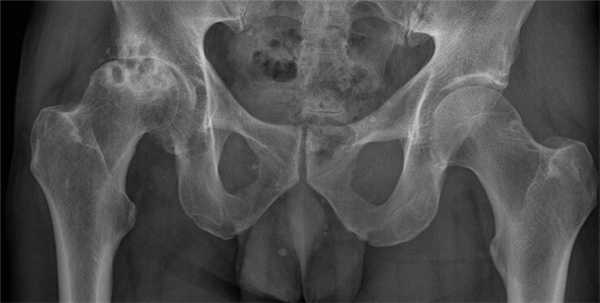

Рентгенологическое исследование

Стадия коксартроза устанавливается проведением рентгенографического исследования. На полученных изображениях отчетливо просматриваются деструктивные изменения в тазобедренном суставе. Это сужение суставной щели, деформация костных поверхностей, формирование остеофитов.

Укорочение ноги на 1 см и более характерно для коксартроза 3 степени тяжести. Причинами уменьшения длины нижней конечности являются сильная мышечная атрофия, истончение и уплощение хрящей, сужение суставной щели, деформация головки бедренной кости.

Укорочение ноги